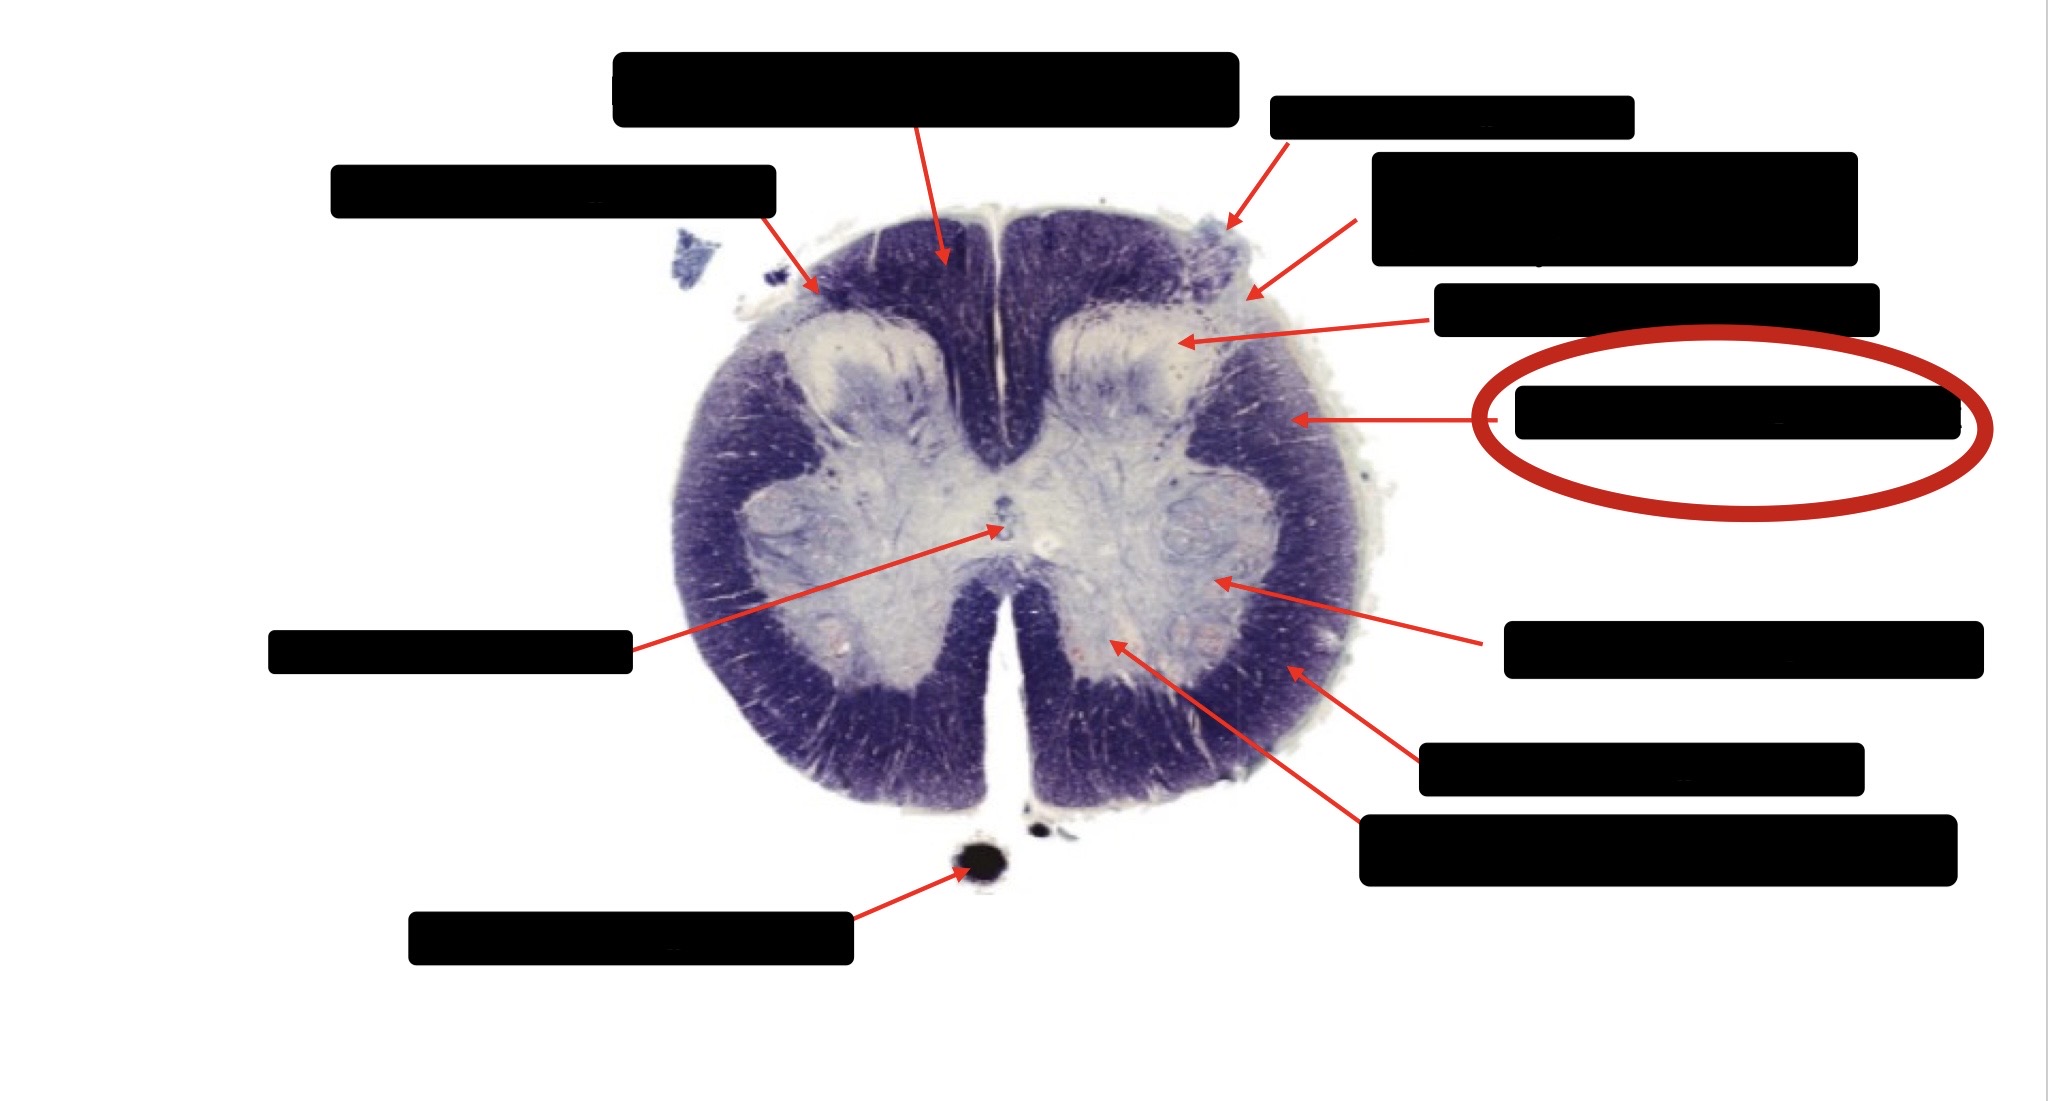

Dorsal Rootlet

Posterior Spinocerebellar Tract

Lateral Corticospinal Tract

Anterior Spinocerebellar Tract

Spinothalmic Tract

Central Canal

Anterior Corticospinal Tract

Posterior Column (Fasciculus Gracilis)

Posterior Column (Fasciculus Cuneatus)

Substantia Gelatinosa

Accessory Nerve Fibers

Anterior Horn Motor Fibers (Accessory Muscles)

Anterior Horn Motor Fibers (Proximal Muscles)

Ventral Root Fibers

Anterior Horn Motors Neurons (Proximal Muscles)